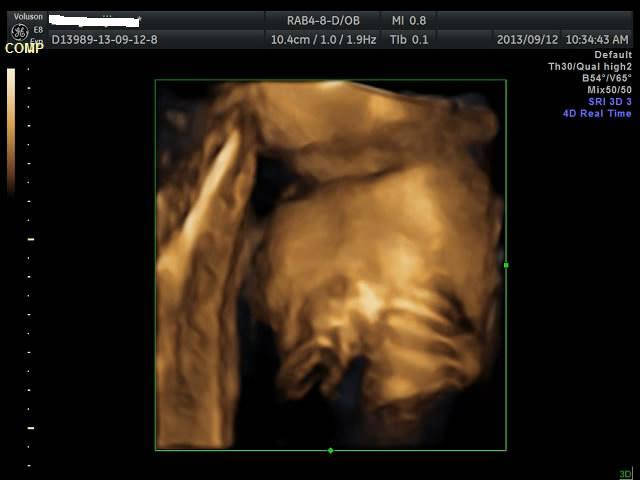

有没有能够帮我看看是千金还是帅哥的朋友?只是好奇是应该准备蓝色衣服还是应该买粉色衣服呢? 点击展开 匿名用户 2013-09-12 20:44 为您推荐: 其他回答 吓死我了... 匿名用户 2013-09-12 20:57 看不出来啊,买米黄色的吧 不论男女,都很好看 匿名用户 2013-09-12 20:57 帅哥的朋友吧,最好选粉红色的 匿名用户 2013-09-12 20:53 要怎么看才好 匿名用户 2013-09-12 20:48 千金,买粉红的 匿名用户 2013-09-12 20:47 相关问题 谁帮我看看是千金还是帅哥! 来看看我家24天的小帅哥,穿粉色衣服么么哒 张凡帅吗?很好奇听说是个帅哥,求解!!!!!!!